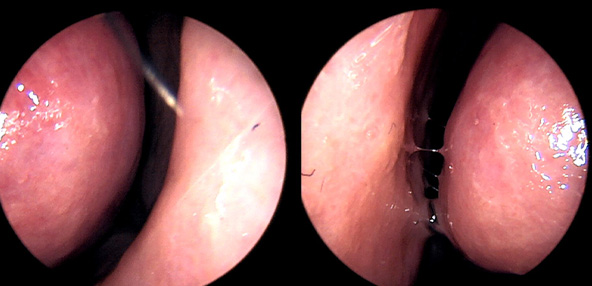

※ 비중격 비염 수술 후 생길 수 있는 부작용으로는 출혈, 감염, 염증이 있을 수 있습니다.

본 사진은 의료기관에서 진료를 본 환자이고, 전후 사진 인물이 동일인이며,동일조건에서 촬영이 되었습니다.